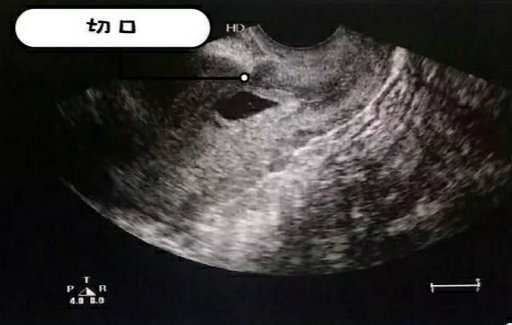

32岁的王女士,停经已有50余天,尿妊娠实验HCG呈阳性,近3天阴道有少量出血,便来到我院产科就诊。产科高玉春主任接诊后,查看了患者自带超声检查报告,报告提示:宫内早孕,孕囊位置低,临床怀疑先兆流产。高主任详细询问了病史后,得知患者既往有一次剖宫产史,不一定是单纯先兆流产,建议患者再次行阴式超声检查。超声检查提示:宫内早孕、孕囊位于剖宫产切口处,考虑瘢痕妊娠。

阴式超声提示瘢痕妊娠